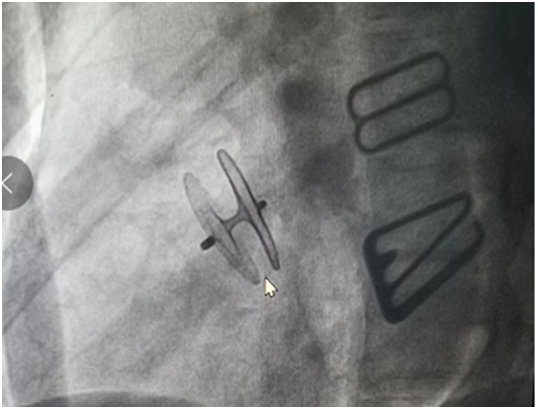

先天性心脏病介入封堵:

肥厚性心肌病经导管射频消融术: